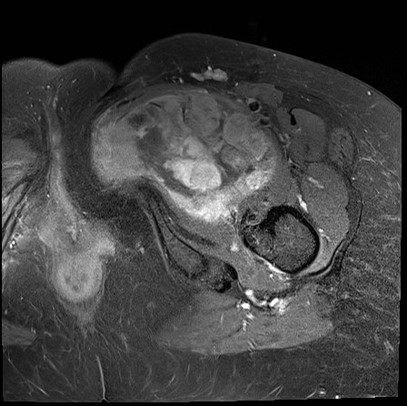

MRI

Sarcoma buttock